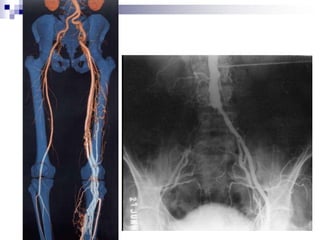

Semiologia Radiológica do tóraxRadiologia Cardiovascular - Anatomia

Semiologia Radiológica dotóraxRadiologia Cardiovascular - Anatomia